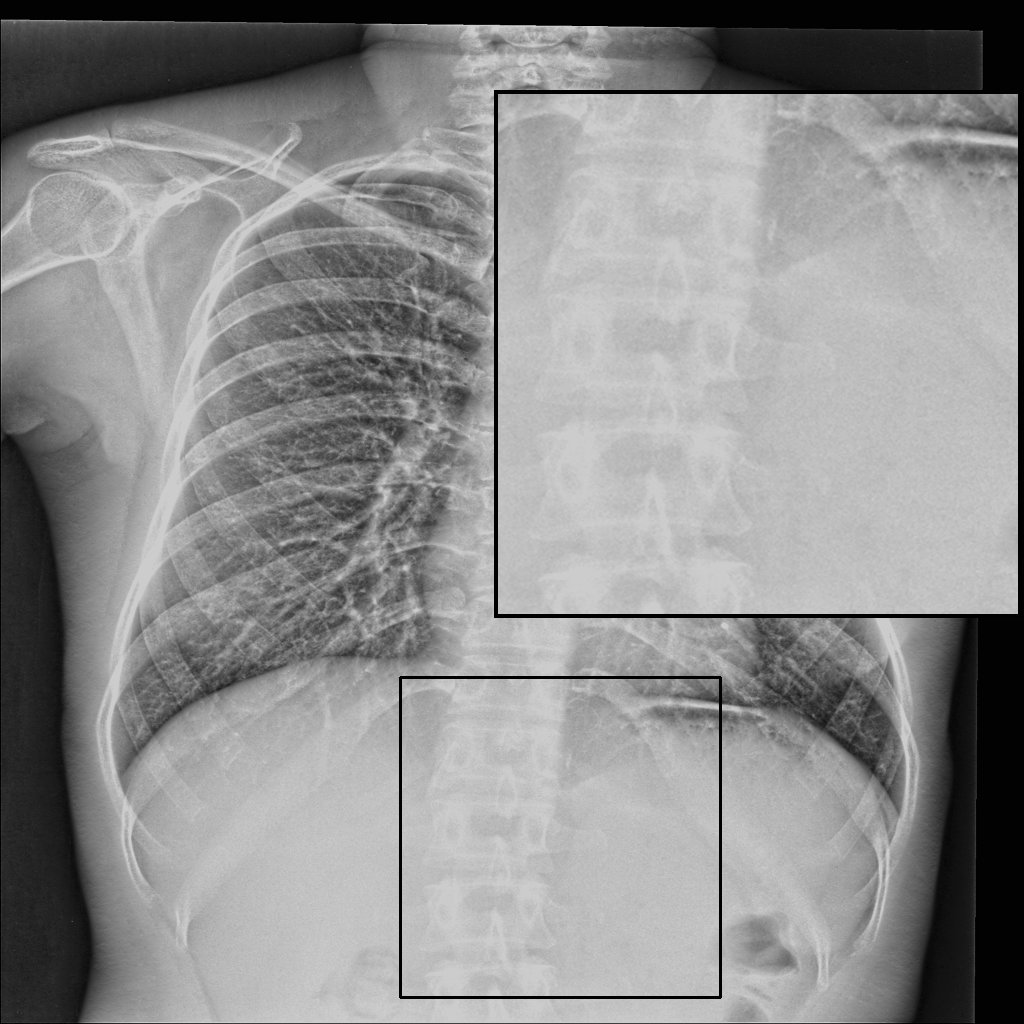

Fig. 3 shows image samples from the above datasets.

Figure 3: Image diversity across four datasets: (a) JSRT, (b) Montgomery County X-ray, (c) NIH ChestX-ray14, and (d) CheXpert

We developed a patch-wise U-Net-based architecture that processes two 512×512512\times 512-pixel regions of interest (ROIs) for each image; one centered on the upper spinal cord and another on the lower spinal cord. As shown in Fig. 3, our datasets exhibit diverse spatial characteristics, with images varying in dimensions (e.g., 2048×20482048\times 2048, 4020×48924020\times 4892, and 1024×10241024\times 1024 pixels) and bit depths (8-bit and 12-bit). This variability in image features poses a significant challenge for creating a robust enhancement model.